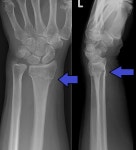

• 요골 | 손목 요골 골절 플레이트 삽입 및 제거 수술 과정, 퇴원, 제거 후기

​ ​ 포스팅 사진 중 일부 징그러운 사진 있습니다 ​ ​ ​ ​ 안녕하세요. 우지직입니다. 손목 요골골절 수술 후기, 플레이트 삽입 및 제거 까지 세세하게 남겨보려고 해요. 모두들 저처럼 다치지 말길.... ​ 때는 2024년도 1월... 열심히 스키와 보드를 타기 시작한지 3일차 ? ​ ​ ​ ​ 네 바로 넘어졌어요. ​ 참고로 전 태어나서 인대...

우먹우먹(2025-12-28 09:00:00)

• 요골 | 손목 골절 수술과 입원 후기 -원위요골, 척골 골절 플레이트 삽입 경험담

이틀에 한 번씩 병원에 가서 소독을 받았어요. 소독은 수술후 총 2주간 해야한다네요. ​ 깁스에 관한 이야기는 다음에 또 포스팅 할게요 다들 힘내세요!^^ ​ #손목골절 #손목골절수술 #수술후기 #플레이트삽입 #척골핀 #재활운동 #골절치료 #골절입원후기 #손목골절후기 #손목수술 #손목골절입원후기 #요골척골 #손목요골...